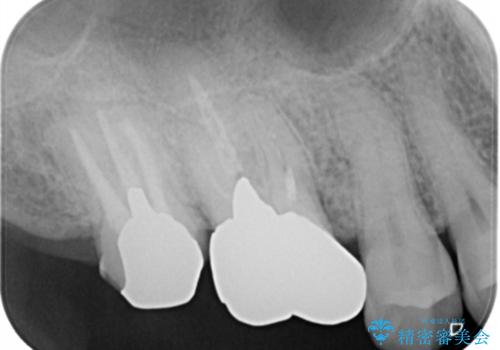

- 右上大臼歯の被せ物が取れたので作り直しを希望された患者様です。

被せ物は白くしたいとのことだったのでフルジルコニアクラウンでの治療を選択しました。

根管治療も必要だったので金属の土台を除去し、新しく土台を立て直した上で被せ物を装着しています。